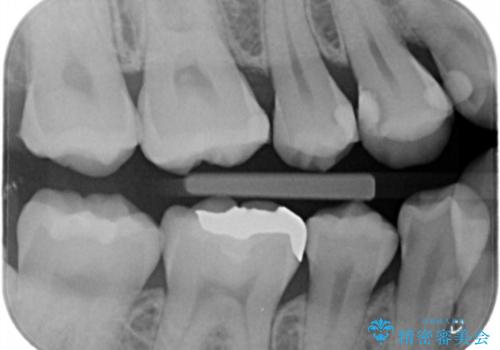

- 歯の健診にて来院。

レントゲンを撮った時にう蝕があったため、拡大鏡下でう蝕が残っていないか確認し

セラミックの詰め物(e-maxインレー)にて治療を行いました。